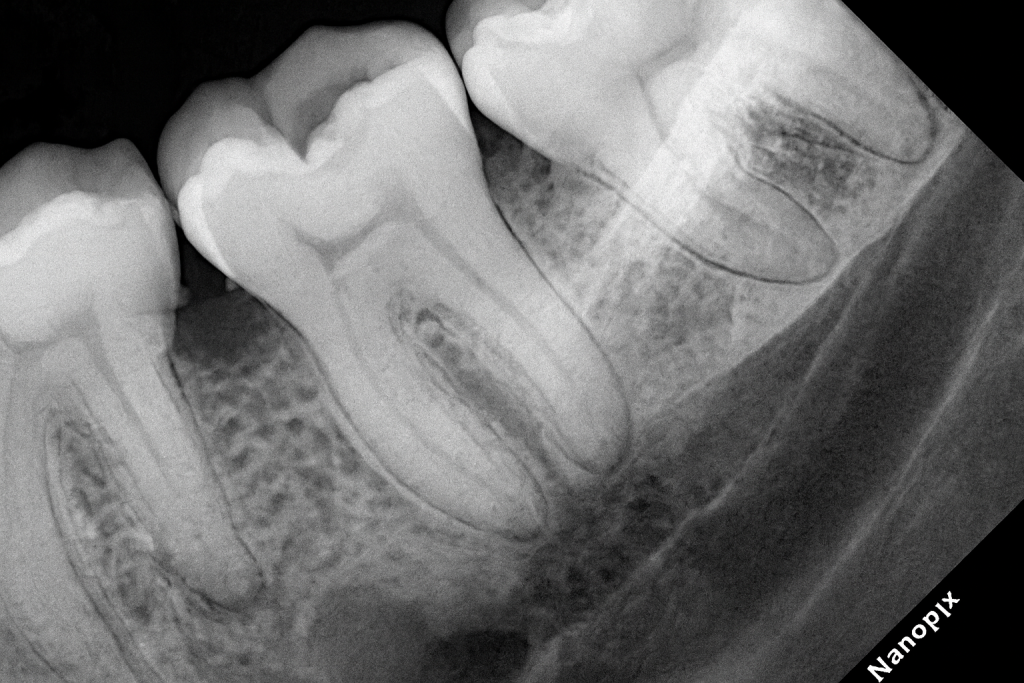

A posterior molar presented with primary occlusal caries confined to enamel and dentin (Fig 1). Under rubber-dam isolation, caries was removed conservatively using a round bur and spoon excavator, preserving peripheral enamel. The cavity design was limited to the carious lesion with no additional mechanical extension.

- Fig 1: Pre-operative view showing occlusal caries.

- Fig 2: Cavity preparation under microscope isolation.